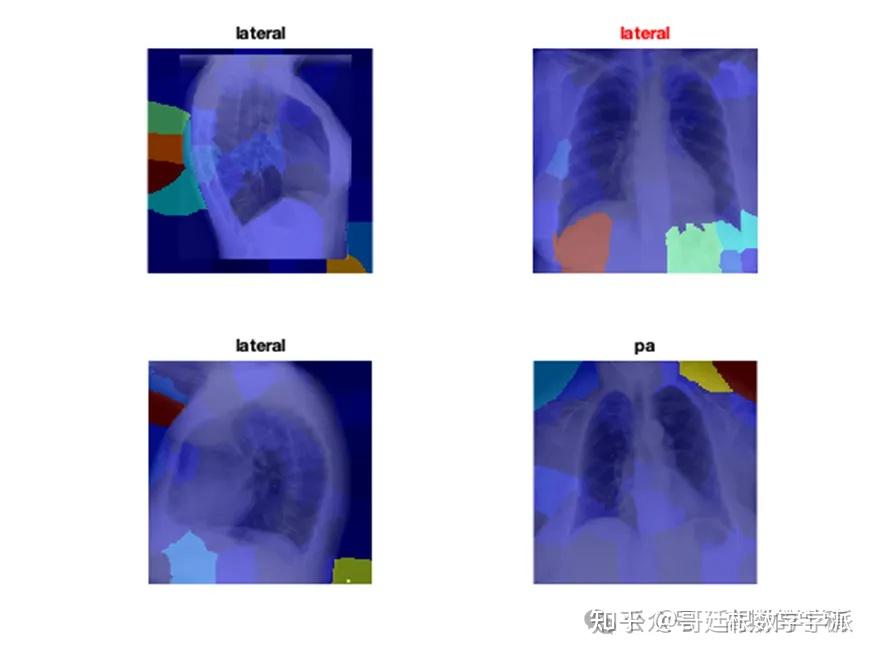

医学图像的深度学习可解释性(MATLAB R2021B)